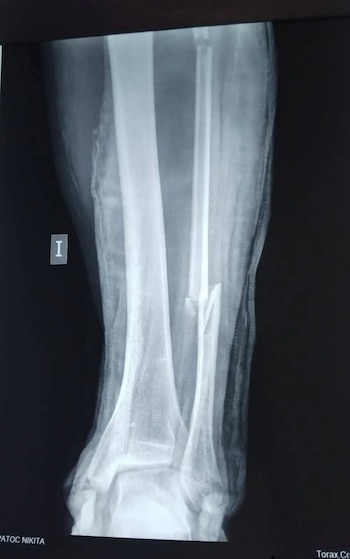

El turista ruso Nikita Ipatov enfrenta la posibilidad de perder la movilidad tras sufrir una grave fractura de tobillo en el sector de Tamborreal, en la provincia del Santa, región Áncash. Durante su travesía mundial en bicicleta, Ipatov fue atropellado por un vehículo cuyo conductor se dio a la fuga, dejando al ciudadano extranjero abandonado en la vía.

La urgencia de una intervención quirúrgica se debe a la complejidad de la fractura, que compromete seriamente su recuperación. Sin embargo, Ipatov no cuenta con seguro médico estatal ni privado, lo que dificulta su acceso a los tratamientos necesarios y retrasa su atención especializada.

El accidente salió a la luz luego de la denuncia pública realizada por ACIPER, organización que alertó sobre la precaria situación del ciclista. Tras el atropello, Ipatov fue trasladado al hospital La Caleta, donde, luego de la evaluación médica correspondiente, se confirmó la gravedad de la fractura y la necesidad urgente de una cirugía para evitar secuelas permanentes.